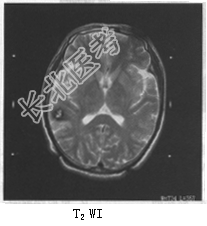

- 单项选择题患者女,36岁。抽搐半年, 近10余天头痛加重,MRI检查如图。最可能的诊断是

A、胶质瘤

B、脑膜瘤

C、动静脉畸形

D、海绵状血管瘤

E、蛛网膜囊肿